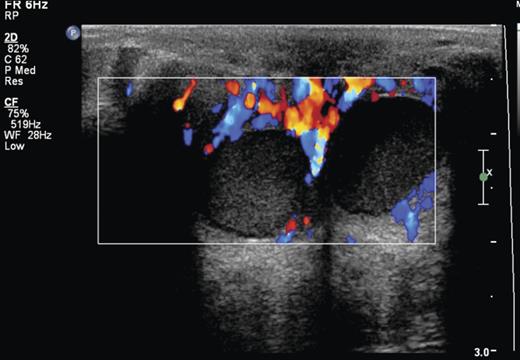

Sonography is the radiological modality that best characterizes retroareolar cysts [1, 4–6]. Garcia et al. [4] in a review of USS in the adolescent breast describe asymptomatic retroareolar cysts presenting as anechoic masses in the breast tissue. The cysts can be multiple in number, round or lobular in shape and contain internal septations or isolated echoes (Fig. 1; [4, 5]). Garcia et al. [4] further describe inflammatory retroareolar cysts to contain echogenic debris, fluid filled levels, internal septations and increased peripheral vascularity [4]. This correlates with our sonographic findings (Fig. 2) and Huneeus et al.'s [1] series who noted the enhanced vascularity only in the symptomatic cyst [1]. Interestingly, Huneeus et al. [1] also reported the presence of bilateral asymptomatic cysts in almost half of their patients.